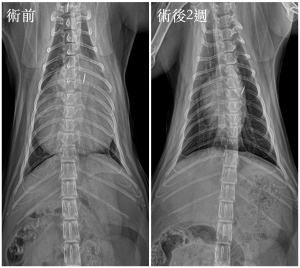

手術順利完成後,兩週複診X 光追蹤,可見心臟、肺臟與肝臟位置都恢復正常,小貓也恢復得很好喔